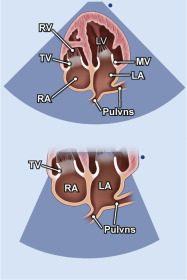

| 2.23. Mặt cắt 4 buồng từ mỏm khu trú vào các tĩnh mạch phổi |

Cửa sổ siêu âm từ mỏm tim

Mặt cắt 4 buồng Tối ưu hóa hình ảnh để khu trú vào nhĩ trái và các tĩnh mạch phổi |

Các tĩnh mạch phổi (Pulvns) Nhĩ trái (LA) Van hai lá (MV) Thất trái (LV) Nhĩ phải (RA) Van ba lá (TV) Thất phải (RV) |